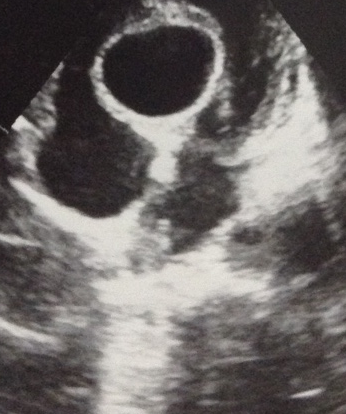

A 35-year-old female presented with a history of fatigue, palpitations, syncopy, and heaviness of chest for the past year. Her symptoms were more pronounced on exertion and relieved on rest. She did not have any other associated problems. She did not have a significant past medical or surgical history. She was afebrile with Hb. of 13.1 g/dl, WBC 10*10^9/L on admission. Her blood type was A+, and HCV and HIV blood tests were negative. Echinococcus granulosus IHA titer was less than 1:16 (negative). On two-dimensional transthoracic echocardiography EF was 65% and there was evidence of LVOT obstruction. A cystic mass measuring 40 × 35 mm within the basal interventricular septum was discovered (Figure 1). Computed tomography of the chest showed a cyst in the interventricular septum and no other cysts were found (Figure 2). MRI showed the brain to be normal.